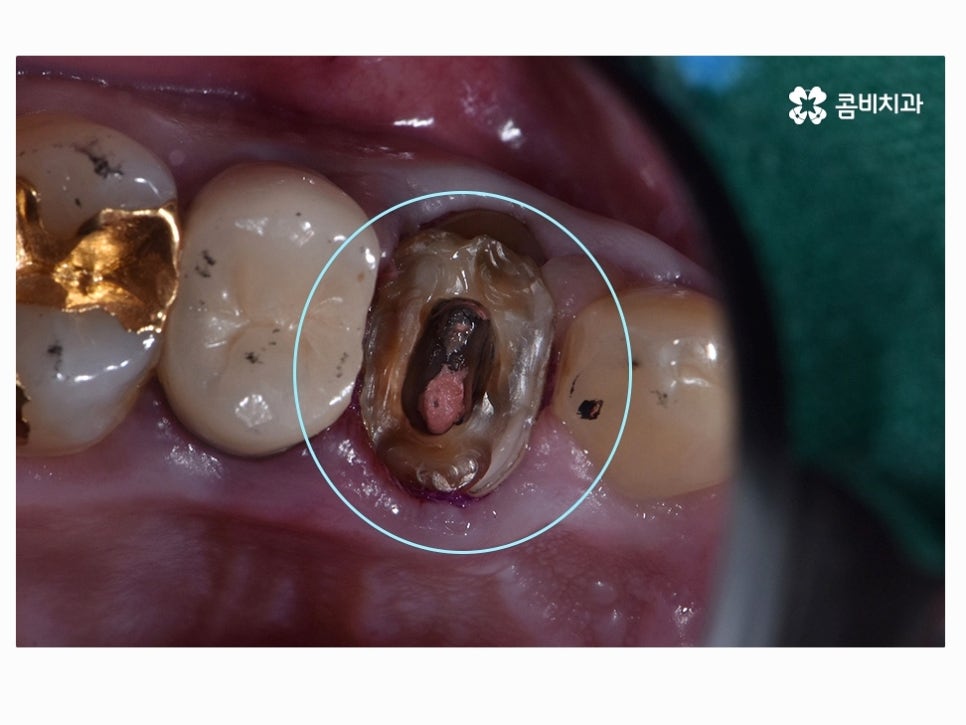

다음 보시는 사례에서도 치아 사이의 청결 관리가 제대로

이뤄지지 않아서 주변 잇몸이 심하게 부은 사례라고 할 수 있는데요.

평소에 치아에 불편한 느낌이 있어도 이미 예전에 크라운 치료나

인레이 등의 치료를 했던 경우에 치아 상태를 눈으로 보기 어렵기 때문에

통증이나 잇몸질환이 당장 발생해도 참아보다가 명동치과

뒤늦게 내원하시는 경우를 참 많이 볼 수 있어요.

이미 과거에 충치 치료를 했다고 하더라도 치료 후 수년간의

시간이 흐르면 치료에 쓰인 접착제가 녹거나 치료재와

치아 사이의 공간이 발생하여 내부 충치로 이어지는 경우가 있는데요.

충치를 인레이 혹은 크라운 치료로 이미 했더라도 개인에

따라 식습관, 생활환경이 다르겠지만 약 7~10년 이상 사용을

했다면 교체가 필요할 수 있기 때문에 주기적으로 검진하면서

이러한 내부 충치에 대한 예방을 잘 하실 필요가 있어요.